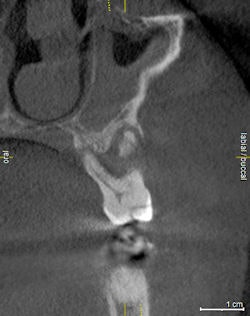

A 29-year-old woman presented for examination and consultation to diagnose a mildly symptomatic lower left second molar. Her previous dentist recommended she visit an endodontist for retreatment of this tooth.

Oral exam revealed a lower left second molar tooth with class III mobility and severe occlusal wear. Periapical pathology was present because of a poorly treated root canal. A CBCT scan gave us a clear understanding that tooth #18 was hopeless and was literally floating in pathology.

Incidental findings were present: a mesiodens in the area of #9 with an associated asymptomatic periapical lesion.